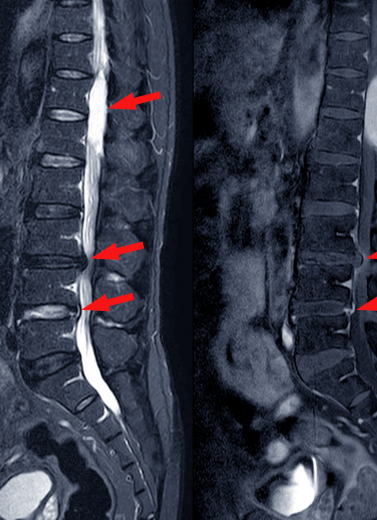

Slip Disc / Herniated Disc

Sciatica and Nerve Compression

Spinal Stenosis

Degenerative Disc Disease